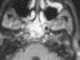

Cranioectodermal dysplasia and bone dysplasia

Osteosclerosis